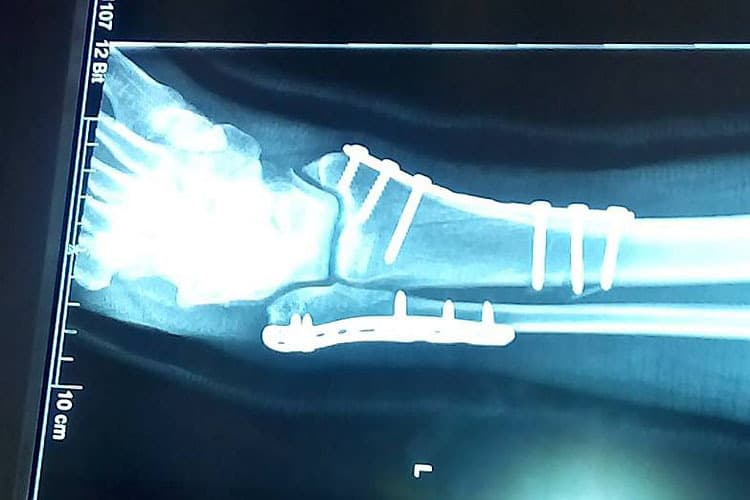

Beim ersten Rennen zur Seitenwagen-Weltmeisterschaft 2017 verunglückte das österreichische Duo Günther Bachmaier und Manfred ""Yeti" Wechselberger. Beim heftigen Einschlag in die Mauer wurde der Beifahrer aus dem Gespann geschleudert. Mit zahlreichen Knochenbrüchen wurde er ins Krankenhaus von Le Mans gebracht, wo der Knöchelbruch sofort operiert wurde.